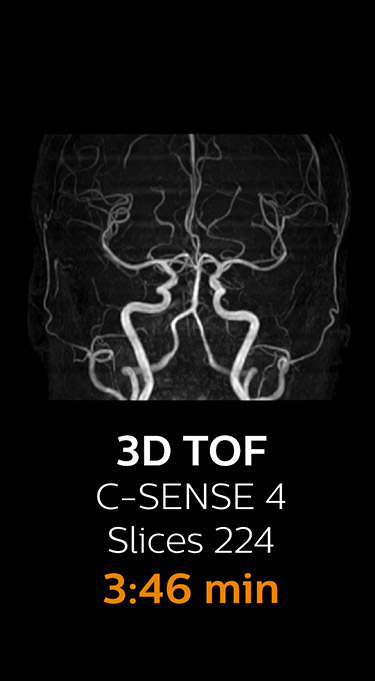

Fast MRI of cervical spine

With Compressed SENSE, the scan time for the routine cervical spine examination at KNC was reduced from 13:11 to 9:52 minutes, which corresponds to 25% reduction.

MRI examination of the cervical spine with Compressed SENSE

Ingenia 3.0T CX

Scan time 9:52 min. (was 13:11 min. without Compressed SENSE)